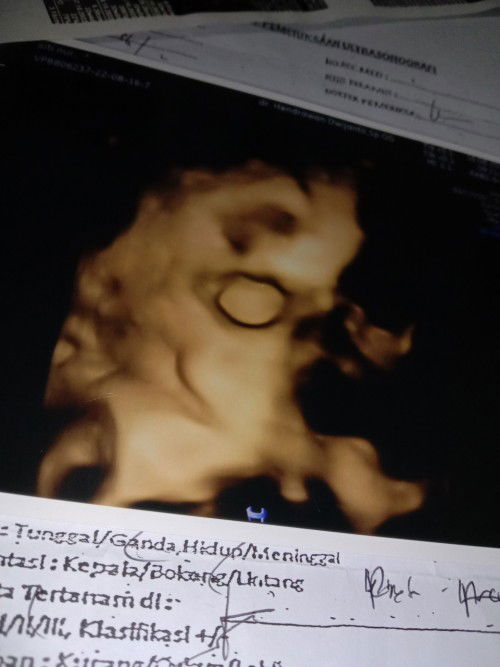

Kandungan Kembar. Kmrn USG dinyatakan kembar pd usia 32Week. Skrg udah 36week, bngun tidur suka sakit kyak ada urat yg ketarik gitu. Itu kenapa ya? Apa kram, kaget atau gimana? Pergerakan janin jga suka di pinggir pinggang . Kmrn USG posisi bagus kepalla udah dibawah. Tapi kok bergerak di pinggir ya? Apa msih bisa berubah posisi?#bantusharing #seriusnanya